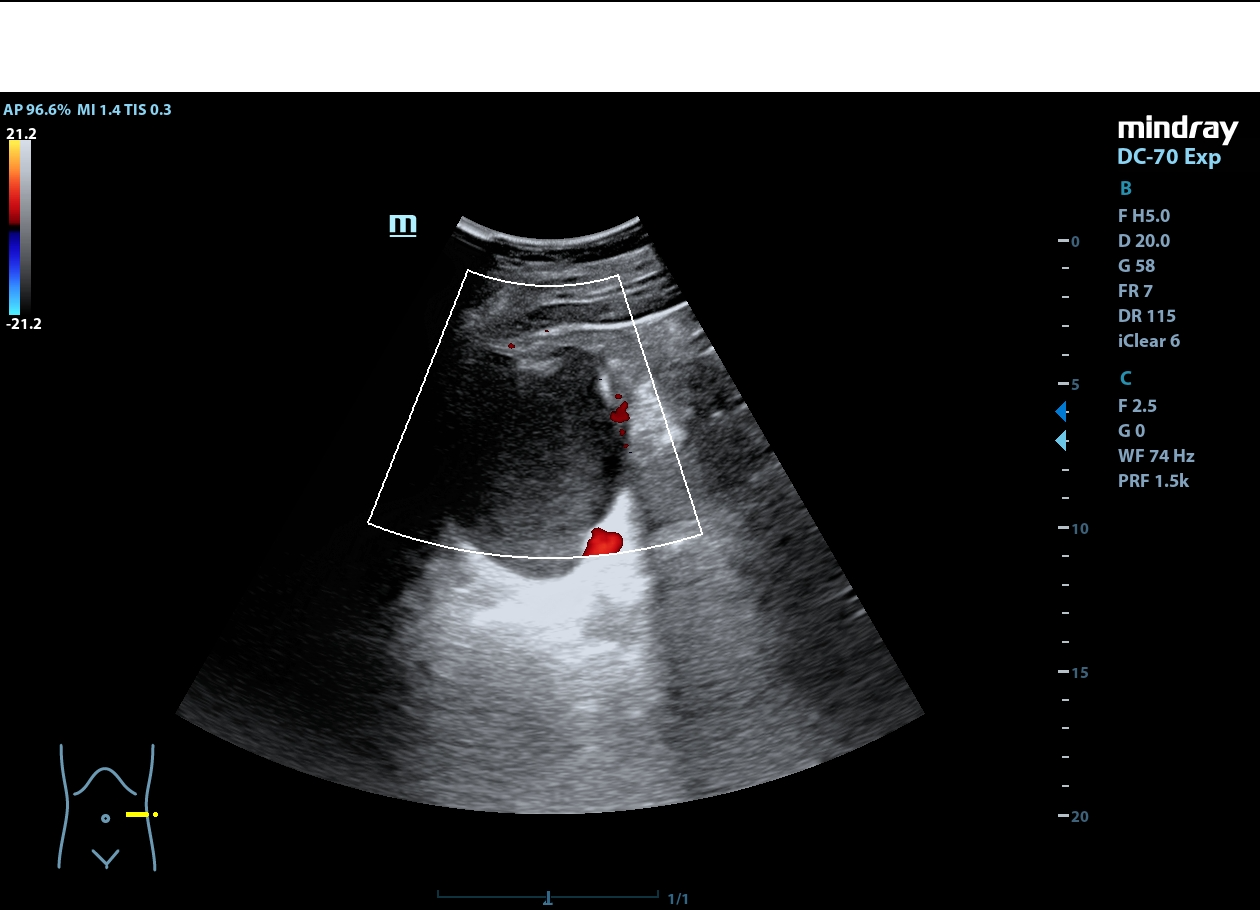

Riñón derecho de ecoestructura conservada, con dilatación pielocalicial grado I. Riñón izquierdo con adelgazamiento cortical y ureterohidronefrosis grado IV, sin poder localizarse el origen de la obstrucción, ausencia de jet ureteral izquierdo. Hallazgos sugestivos de síndrome de la unión pieloureteral.